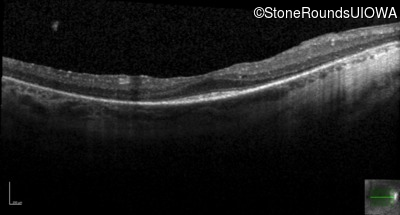

Optical Coherence Tomography - Left - 20/50

Exemplar / OCT Stack